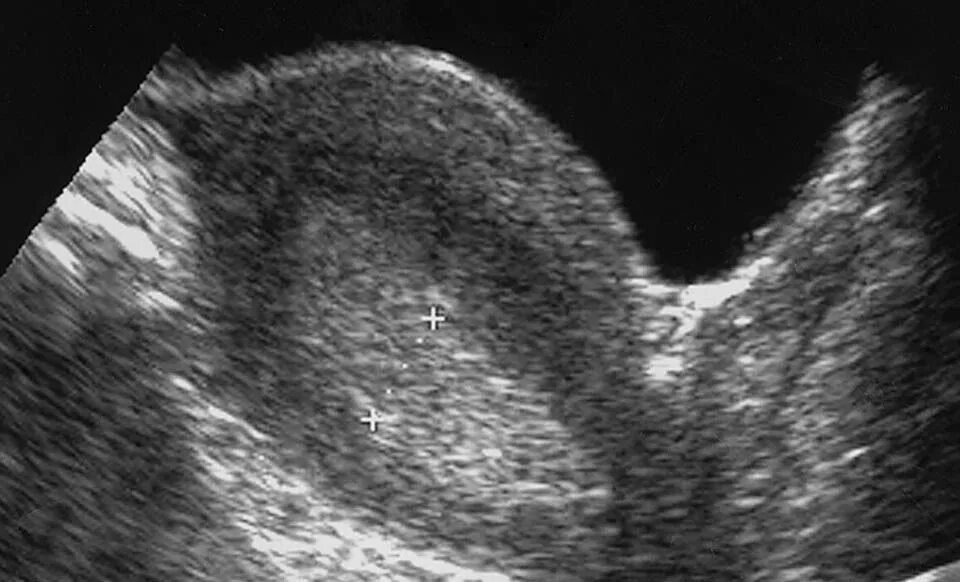

Гиперплазия эндометрия матки по узи. кистозная гиперплазия эндометрия на узи. железистая гиперплазия эндометрия по узи.

Железистая гиперплазия эндометрия узи. гиперплазия эндометрия на узи. гиперпластические процессы эндометрия узи. атипическая гиперплазия эндометрия узи.

Атипическая гиперплазия эндометрия узи. гиперплазия эндометрия на узи. эндометрия матки узи гиперплазия эндометрия. картина гиперплазии эндометрия на узи.

Атипическая гиперплазия эндометрия узи. железистая гиперплазия эндометрия узи. ультразвуковые критерии гиперплазии эндометрия. гиперпластические процессы эндометрия узи.

Железистая гиперплазия эндометрия узи. полип и гиперплазия эндометрия на узи. гиперплазия эндометрия узи критерии. кистозная гиперплазия эндометрия на узи.

Гиперплазия эндометрия мфя. железистая гиперплазия эндометрия узи. эхограмма гиперплазии эндометрия. гиперплазия эндометрия узи критерии.

Атипическая гиперплазия эндометрия узи. гиперплазия эндометрия на узи. гиперплазия железисто кистозная эндометрит. железистая гиперплазия эндометрия узи.

Гиперплазия эндометрия на узи. гиперпластические процессы эндометрия узи. эхограмма гиперплазии эндометрия. железистая гиперплазия эндометрия узи.